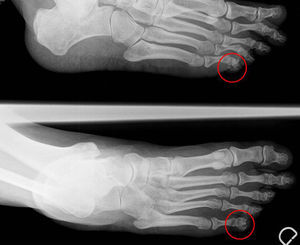

Mujer de 57 años, sin antecedentes patológicos, aficionada al senderismo, que consultó por la aparición de una lesión subcutánea de 5mm en el quinto dedo del pie izquierdo, de 12 semanas de evolución. La lesión era intensamente dolorosa y no había experimentado cambios. La radiografía simple del pie reveló la presencia de una pequeña calcificación en el borde lateral de la falange distal del quinto dedo del pie izquierdo (fig. 1). Analítica incluyendo marcadores inflamatorios, calcio, fósforo y ácido úrico dentro de la normalidad. El dolor desapareció tras la extirpación (fig. 2). No ha reaparecido en los 20 meses de seguimiento.